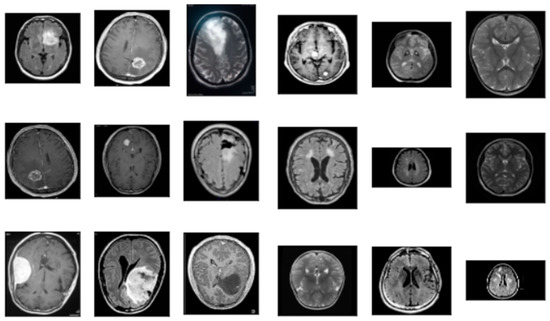

3.1. Data Collection

3.1.1. Data Preparation

| Folder | Description |

|---|---|

| Yes | Folder yes contains 1500 Brain MRI Images that are tumors |

| No | Folder no contains 1500 Brain MRI Images that are non-tumorous |

| Pred | This folder contains 60 Brain MRI Images that are both tumors and non-tumorous to be used to validate the model in the end |